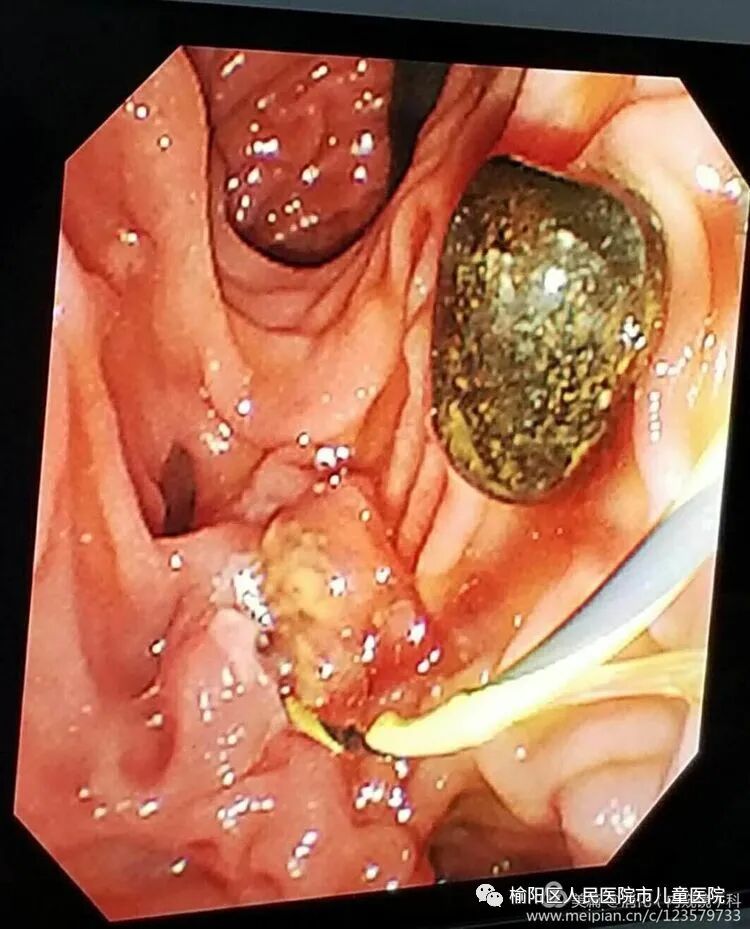

患者郭某某,女,78岁,因“腹痛伴大便不成形6个月”就诊,肠镜检查如下:

诊断明确,收住院,评估手术风险,向患者家属交代病情及术中术后风险,进行内镜下粘膜剥离术。

这就是内镜黏膜下剥离术ESD(endoscopic submucosal dissecfion)的整个过程。随着内镜微创技术的发展,越来越多的早期胃癌、肠癌、癌前病变及胃肠黏膜下疾病可完全在内镜下予以切除,免除了更大的手术创伤。